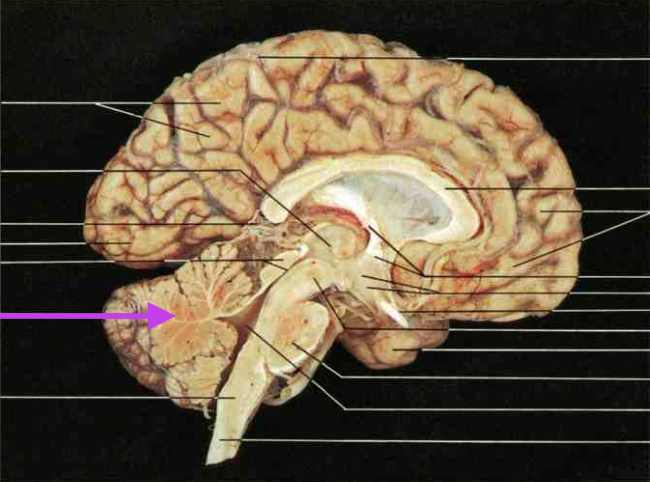

Cerebellum

Pineal Body. Section is cerebrum and diencephalon.

Mamillary Bodies. Section is cerebrum and diencephalon.

27

Interventricular Foramen. Section is cerebrum and diencephalon. Connects the third ventricle to the lateral ventricles.

Lateral Ventricle. Section is cerebrum and diencephalon.

Fluffy stuff on the floor of the lateral ventricle.

Choroid plexus.